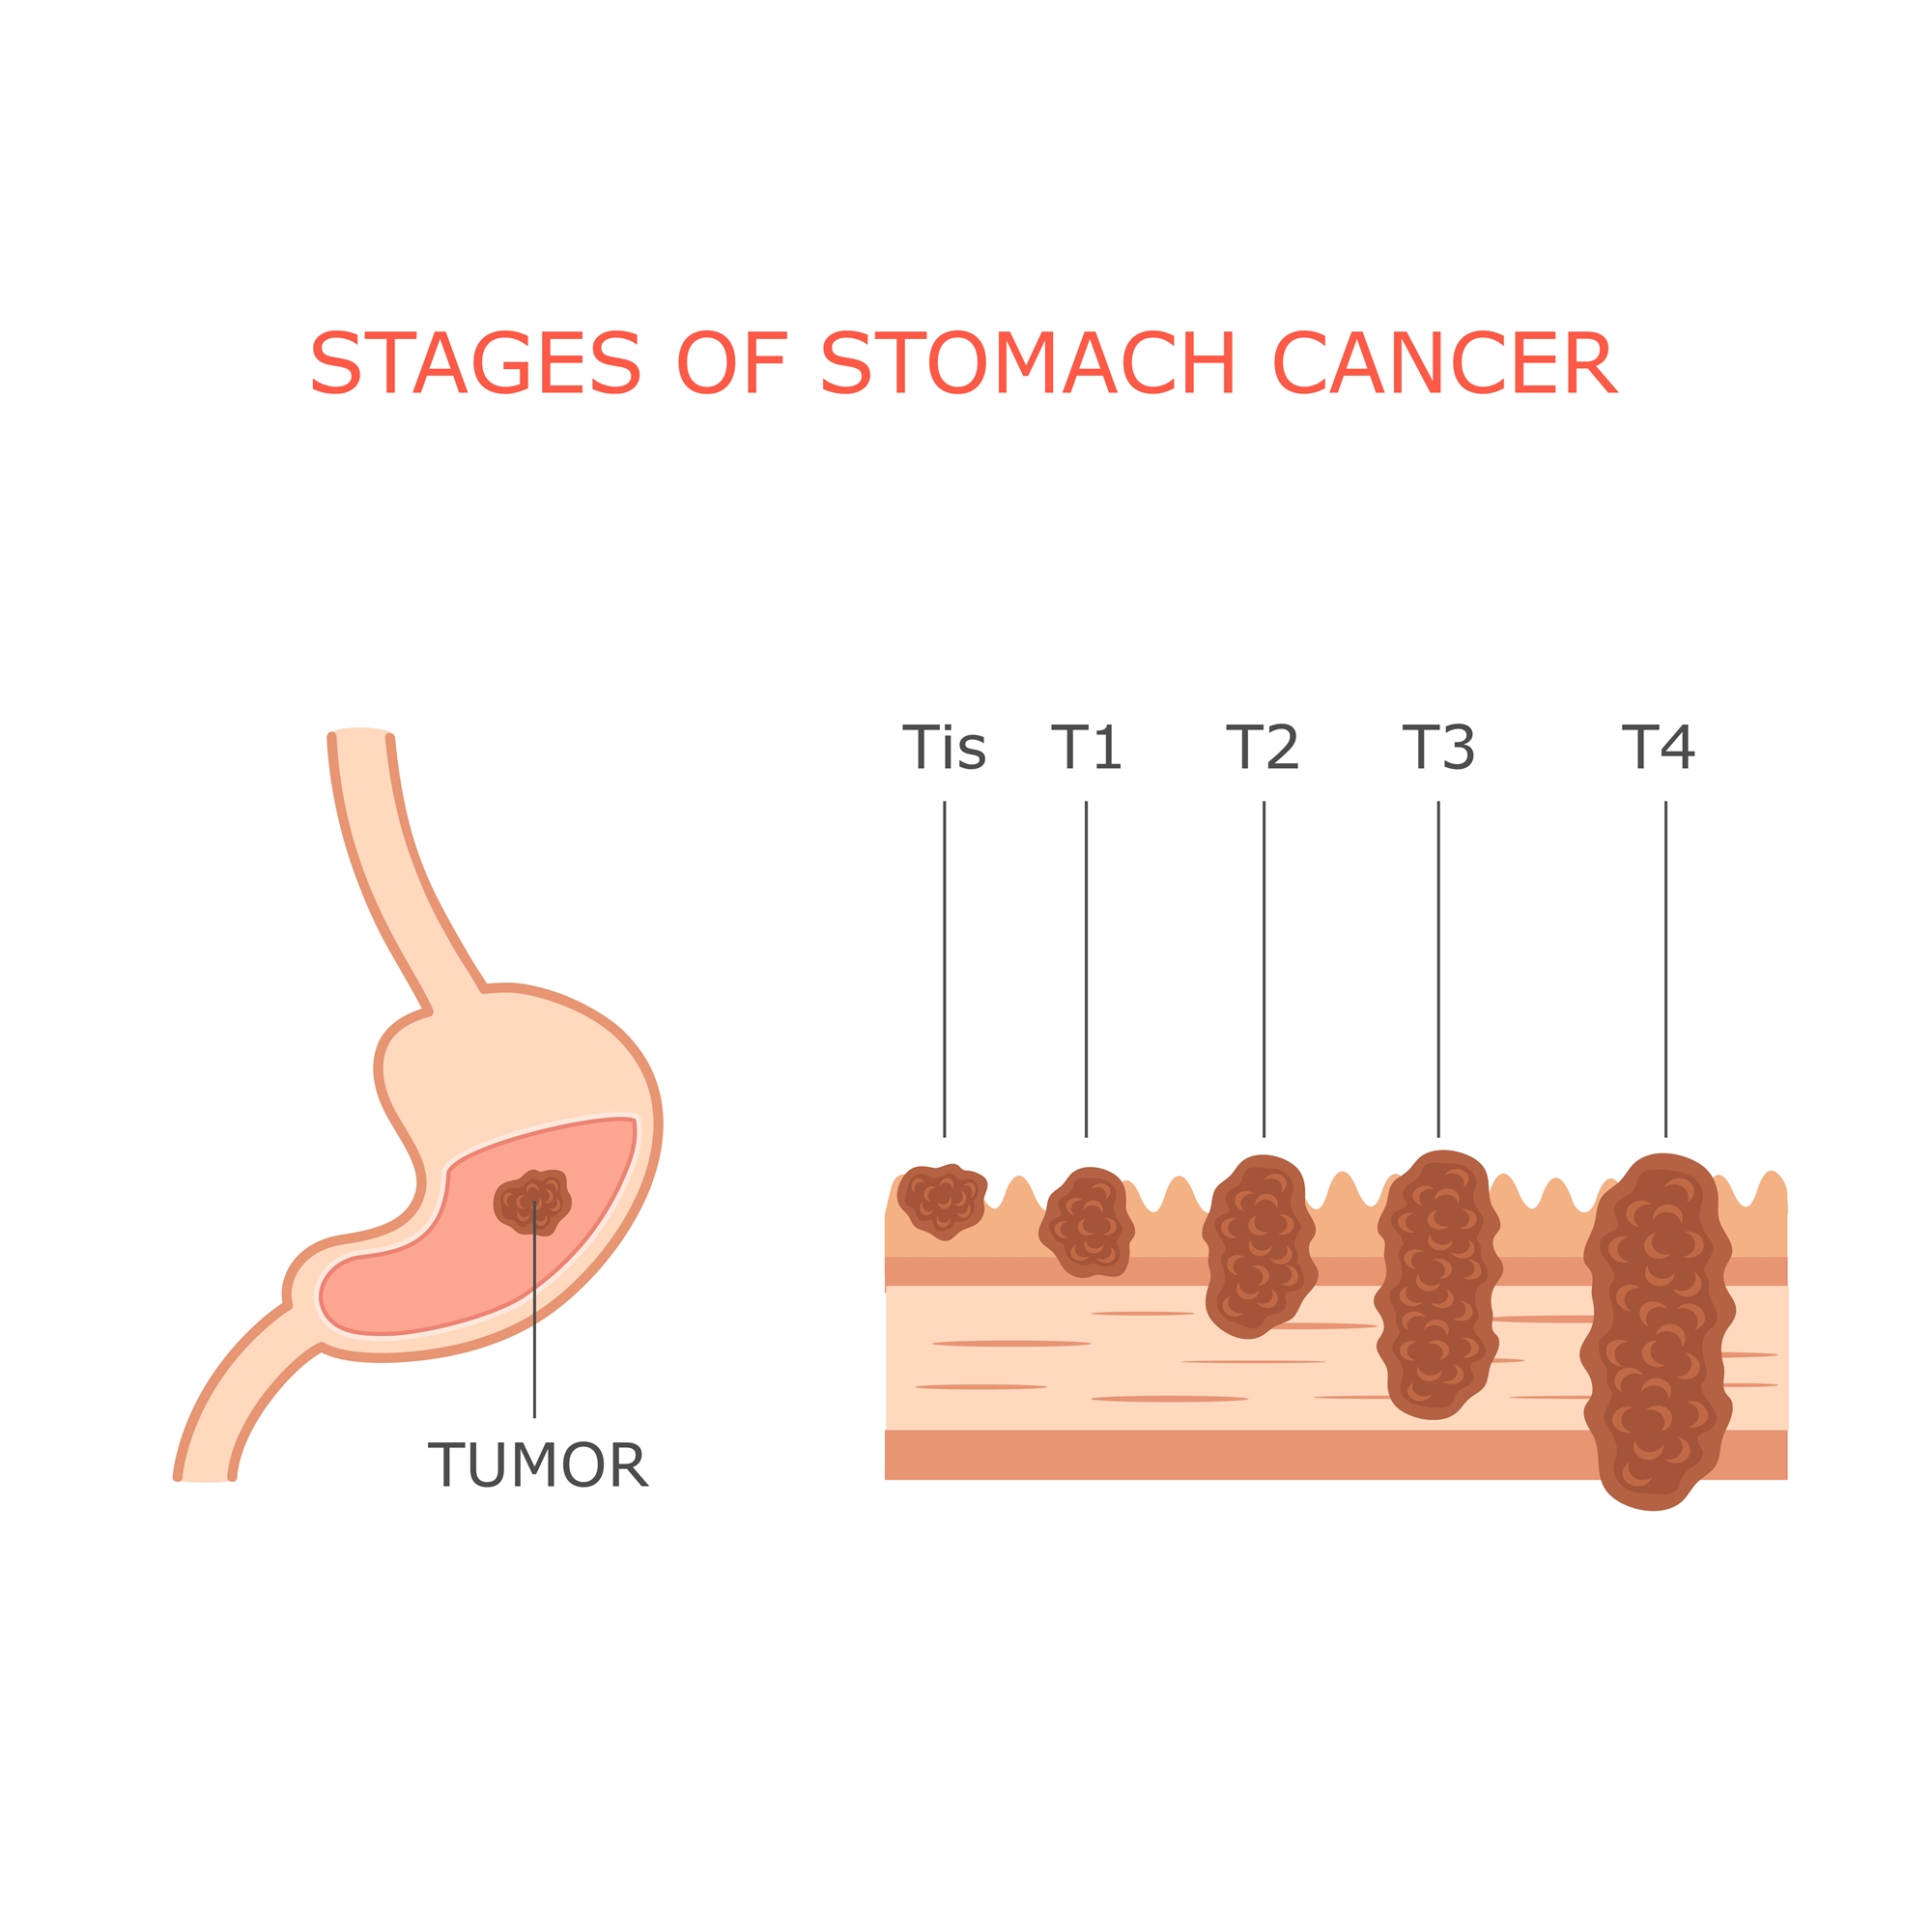

Stages of stomach cancer Royalty Free Vector Image

Stages Of Gastrointestinal Cancer | herxheim.de

Stage 4 Stomach Cancer. What is advanced cancer? | by Zeeva Clinic | Medium

Stage 4 Stomach Cancer. What is advanced cancer? | by Zeeva Clinic | Medium

Stage 4 Stomach Cancer. What is advanced cancer? | by Zeeva Clinic | Medium